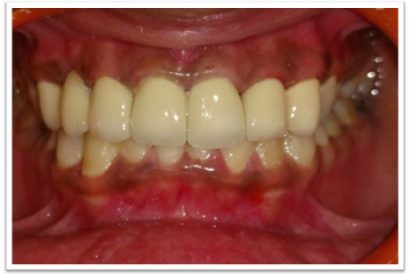

Patient Name:Padma Harkar

Tooth Involved : 11 12 13 21 22 23

Diagnosis : Fluorosis

Treatment : Direct Composite Veneers

Restoration: Direct Composite Using Nanohybrid composite

Stains masked using IVOCLAR EMPRESS COLOUR White And Honey.